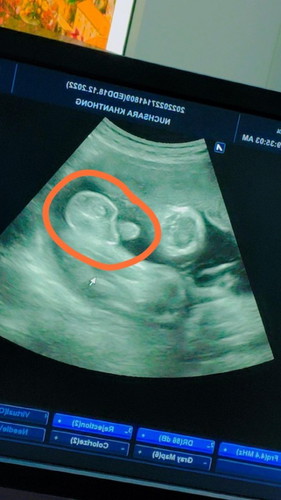

ต้าวลูกชาย 36+4 โชว์จู๋ใหญ่เลย อีก1อาทิตย์เจอกันนะงับ 2,660 กรัม แค่นี้แม่ก็พอใจแล้ว ขอให้หนูแข็งแรงก็พอ✌️❣️🤰